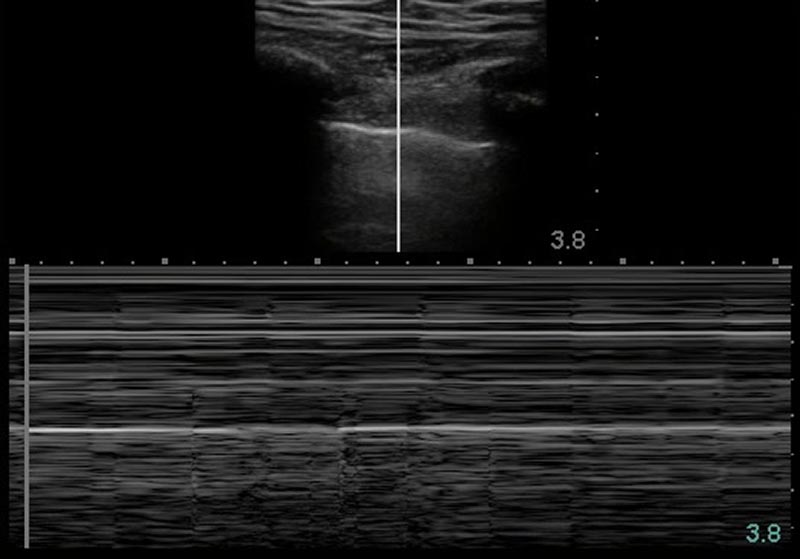

63 yo smoker with extensive copd on home oxygen comes to the emergency department short of breath. The learner should obtain a brief history as they begin interventions as the patient's vital signs are unstable. The learner should use bedside ultrasound to rule out other causes of shortness of breath during the initial presentation and use ultrasound to re-evaluate the patient if there is a change in status.